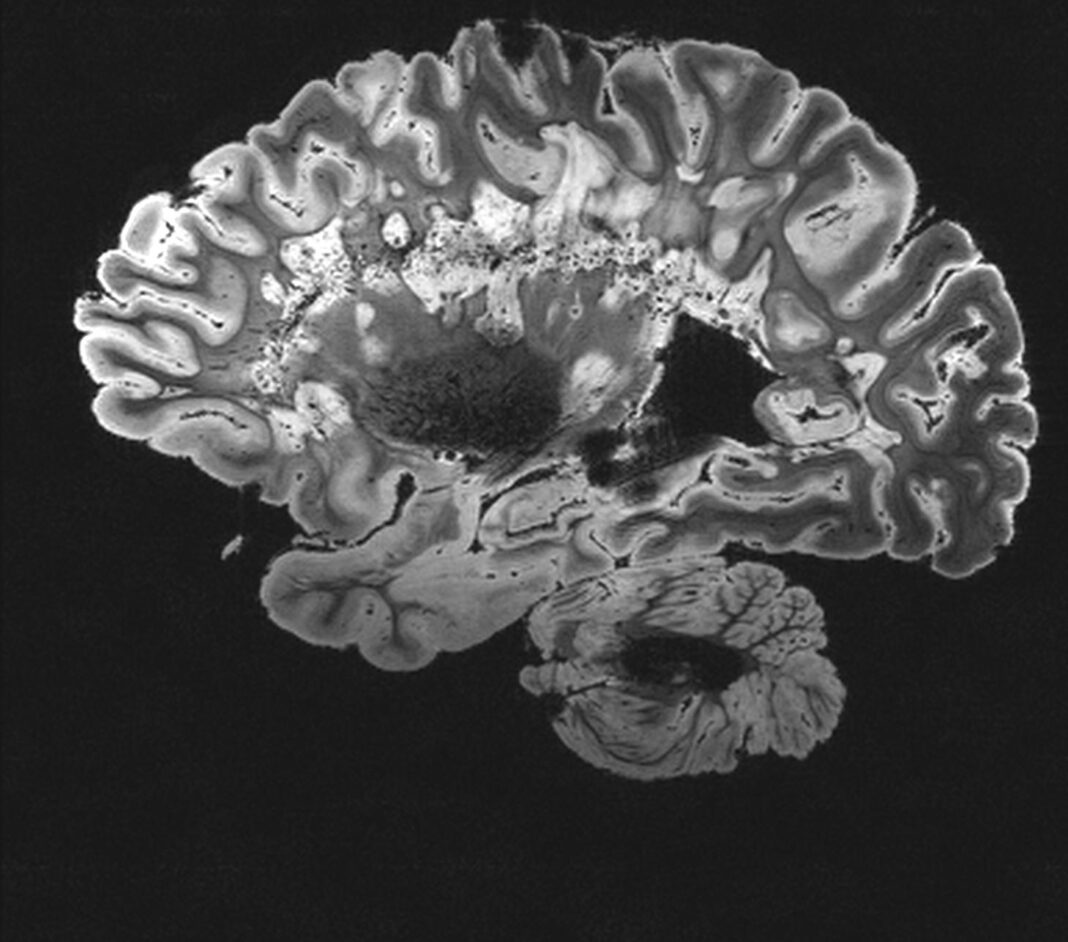

The research comes as the NHS is increasingly using digital tools and artificial intelligence to improve stroke care, including software now deployed across stroke centres in England to help clinicians analyse brain scans and make faster treatment decisions. Updated national stroke guidelines have also placed greater emphasis on early cognitive screening and long-term rehabilitation.